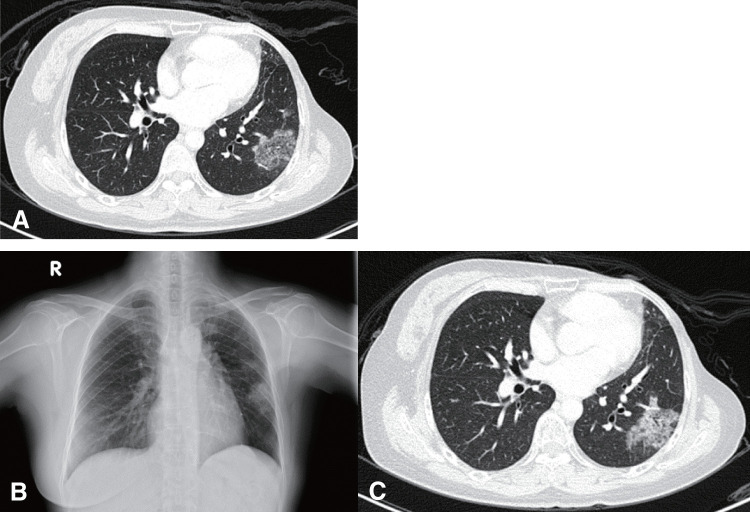

Lipid pneumonia is exceedingly rare, with only a few reported cases to date. A 46-year-old woman with a history of left breast cancer underwent a left-modified radical mastectomy, adjuvant chemotherapy, and radiotherapy. Despite no known exposure to lipids, she presented with chronic non-productive cough and general malaise. Follow-up chest computed tomography revealed progressive ground-glass opacities in the left lower lung, initially suspected to be lobar bronchioloalveolar carcinoma. Surgical intervention was performed for both diagnostic and therapeutic purposes, confirming the lesion as lipid pneumonia upon pathological examination, revealing the presence of foamy histiocytes.